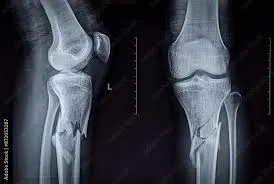

Fractures

are breaks or cracks in bones.

greenstick

Impacted

Closed

Open

Comminuted

Pott’s

Colles’

Stress